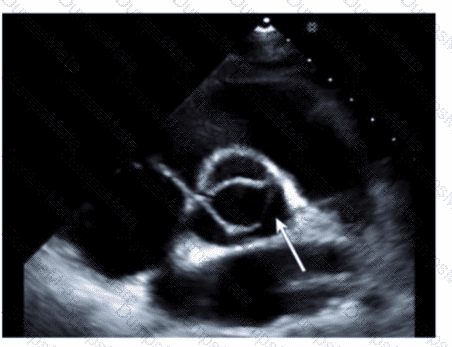

Which finding is shown in this image?

AE-Adult-Echocardiography Question 4

Options:

A.

Chiari network

B.

Left atrial thrombus

C.

Cor triatriatum

D.

Artifact